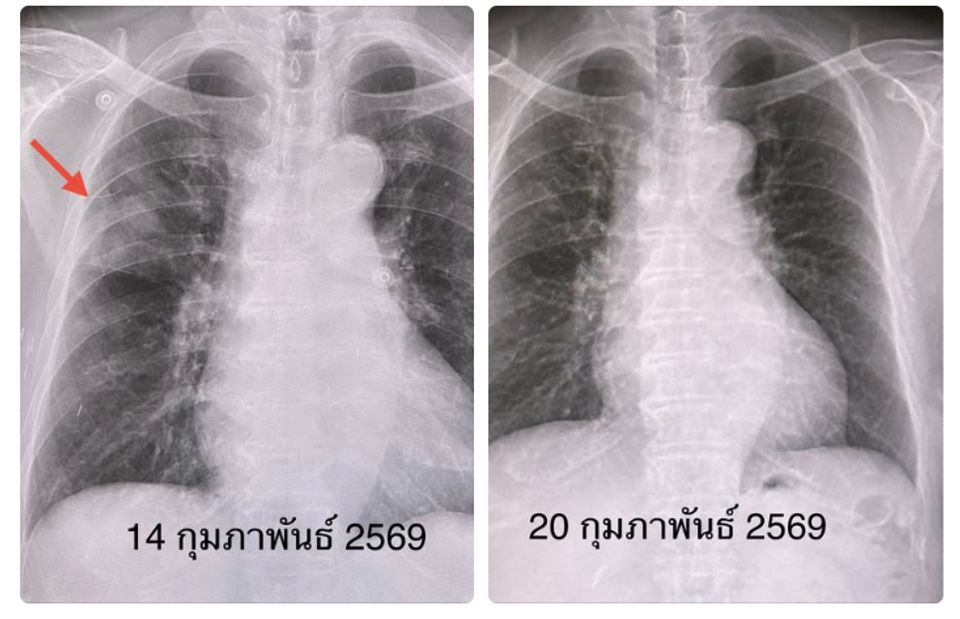

ผลตรวจร่างกาย ไม่มีไข้ ระดับออกซิเจนที่ปลายนิ้ว 96% หัวใจเต้นเร็ว 130 ครั้ง/นาที หัวใจเต้นผิดจังหวะ ฟังปอดปกติ ทำคลื่นไฟฟ้าหัวใจ พบหัวใจห้องบนเต้นระรัว (Atrial fibrillation) ตรวจหัวใจดัวยคลื่นเสียงความถี่สูง (Echocardiogram) ไม่พบความผิดปกติ เจาะเลือด เม็ดเลือดขาวในเลือดปกติ ส่งเลือดเพาะเชื้อ ไม่ขึ้นเชื้อแบคทีเรีย เอกซเรย์ปอด มีฝ้าขาวลักษณะคล้ายก้อนที่ปอดข้างขวากลีบบน แยงจมูกส่งตรวจสารพันธุกรรม RT-PCR พบเชื้อโบคาไวรัส (Bocavirus)

เคสนี้แพทย์วินิจฉัย ว่า โบคาไวรัส (Bocavirus) ทำให้เกิดปอดอักเสบ และภาวะหัวใจห้องบนเต้นระรัว (Arial fibrillation) ในผู้สูงอายุรายนี้ ซึ่งมีโรคประจำตัวเบาหวาน และไขมันสูง หลังให้ยา cordarone หัวใจกลับมาเต้นเป็นปกติ ให้การรักษาตามอาการ ไอลดลง ไม่มีเสมหะ ไม่มีไข้ ติดตามเอกซเรย์ปอดกลับมาปกติในเวลา 6 วัน